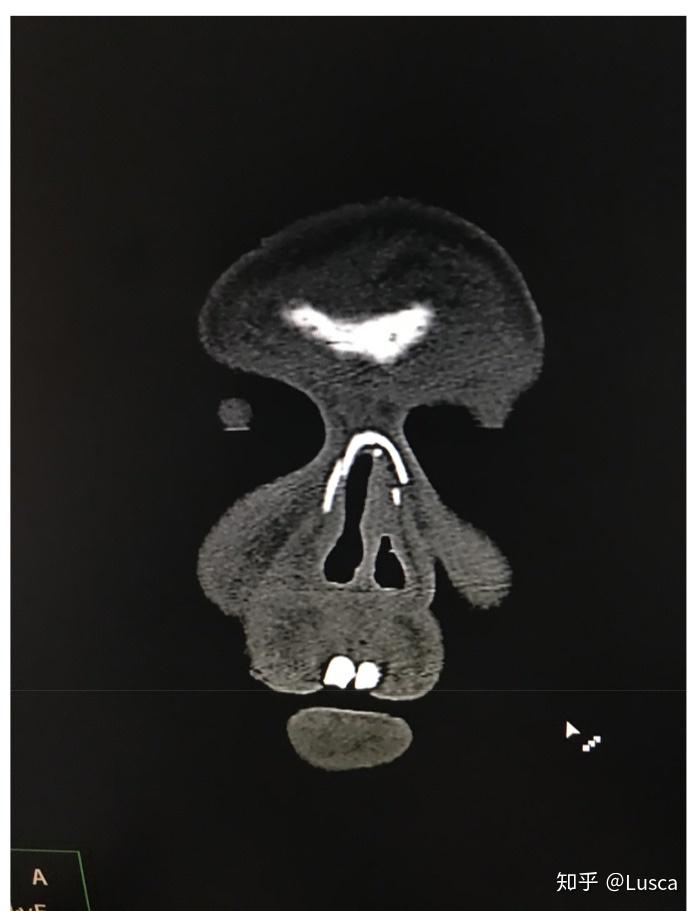

诊断 处理 上颌骨lefort-i骨折,下颌骨颏部骨折.